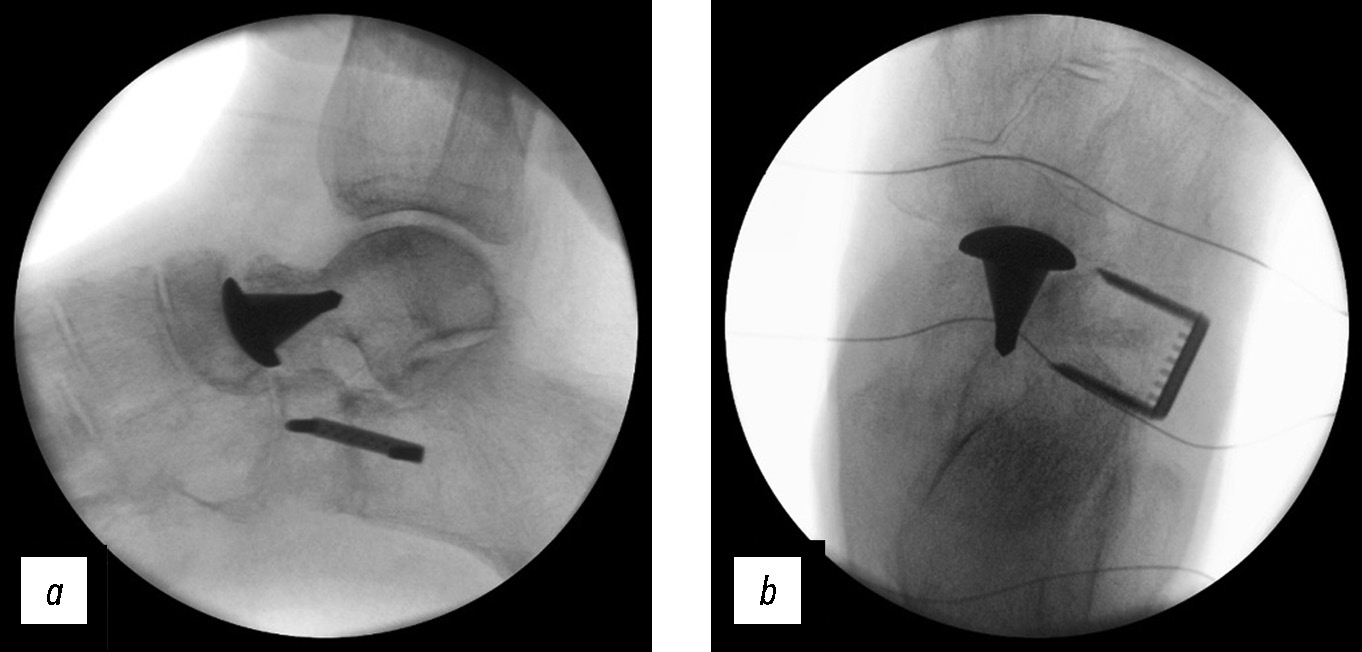

Головка эндопротеза вправлена в суставную впадину ладьевидной кости. После этого выполнены репозиция и остеосинтез переднего суставного отростка пяточной кости. Клинически и с использованием электронно-оптического преобразователя был определён объём движений таранно-ладьевидного сустава. После туалета ран растворами антисептиков рассечённые мягкие ткани ушили послойно (рис. 8).

Рис. 8. Интраоперационные изображения с электронно-оптического преобразователя правого голеностопного сустава и стопы: а — в боковой проекции, b — в переднезадней проекции. Положение имплантата, скобы-коннектора корректное.

Fig. 8. Intraoperative images from the electron-optical converter of the right ankle and foot: а — in lateral projection, b — in anteroposterior projection. The position of the implant and connector bracket is correct.